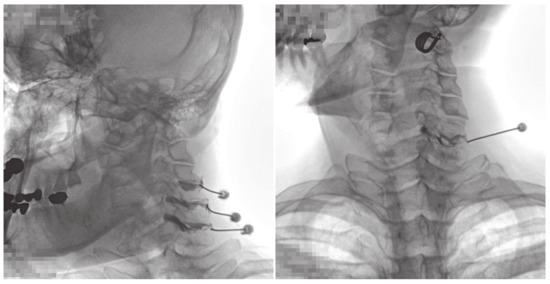

Fluoroscopic Findings of Extra-Cervical Facet Joint Flow and Its Incidence on Cervical Facet Joint Arthrograms

2.2. CFJ Injections/Arthrogram Analyses